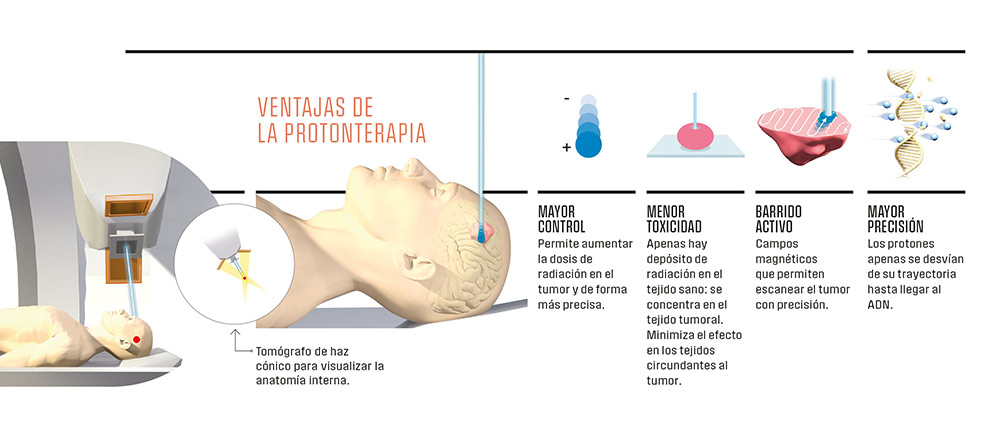

Menor toxicidad y mayor precisión. La terapia con protones permite aumentar la dosis de radiación que se aplica al tumor al tiempo que minimiza dispersiones innecesarias. Y todo ello porque se trata de una radiación diferente a la convencional. Mientras la habitual se basa en un haz de rayos X (fotones), la protonterapia utiliza partículas aceleradas (protones) que pueden dirigirse de forma más precisa. ¿La razón? Las características físicas de los protones, que, por su masa, no sufren alteraciones en su trayectoria. De este modo consiguen depositar la mayor parte de su energía dentro del tumor y, además, al topar con este se frenan inmediatamente y no irradian más allá. La doctora Carmen Ares lo explica con un símil: «Imaginemos la trayectoria de esos haces como si fuera una autopista. En la radioterapia tradicional llegan a la zona que se quiere radiar, pero van depositando ciertas dosis en los tejidos que atraviesan y, además, siempre hay otra dosis de salida». Por eso, la protonterapia está especialmente indicada en tumores que requieren dosis muy altas y que están localizados cerca de zonas u órganos muy sensibles a la radiación y en tumores pediátricos, «ya que los órganos están todavía en desarrollo y es aún más importante evitar irradiarlos», continúa.